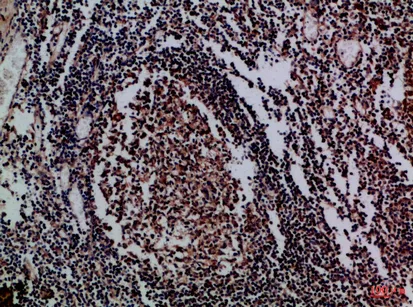

Granzyme M Rabbit Polyclonal Antibody

Cat: APRab11744